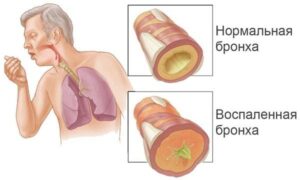

Туберкулез легких является следствием перенесенной ранее туберкулезной инфекции, которая реактивировалась из-за сбоя иммунной системы. Туберкулез — это закрытый казуистический узел в легком размером более 12 мм. Характерной особенностью процесса является его длительное и мало симптоматическое течение, основные причины и диагностические симптомы которого можно найти в этой статье. Что это такое? Туберкулема (от латинского tuberculum — …